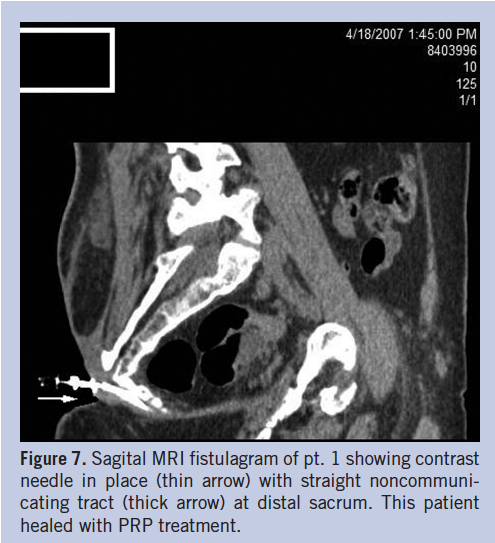

PRP can be a useful alternative in nonhealing sinus tracts. The most important aspect in this series of patients was to ensure proper bacterial control within the sinus tract in order to avoid the development of infection. Thus tracts were treated prior to injection with appropriate antiseptic/antibiotic packing for 1 to 2 weeks. The authors recommend only injecting tracts that are relatively straight, as any curvature in the course of the tract could induce dead space formation and subsequent abscess development. There was a low threshold for imaging via sinogram to avoid injecting long tracts, curved tracts, tracts with significant out-pouching, complex tracts, and tracts with extension into visceral organs, hardware, or infected bone (Figure 7). Of the three patients whose wounds did not heal, two (pt. 10 and pt. 11) had long (> 5 cm) tracts with curved courses and complex anatomy; one (pt. 12) had complex comorbidities and chronic renal failure. All straight tracts with < 5 cm length healed. Injection should start at the base of the wound to fill the entire tract with continuous injection during pullback. PRP injection can be a useful technique in cases of straight, relatively short, persistent sinus tracts.